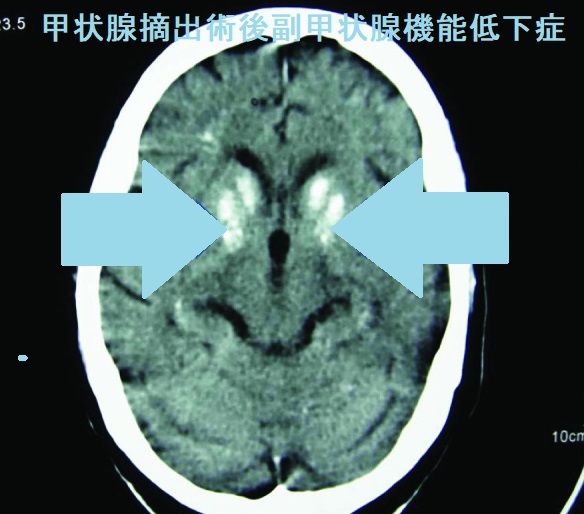

- 精神不穏、不安、抑うつ、知能発育遅延、認知障害、大脳基底核の石灰化(92%)

- 歯の発育障害、白内障(約35%)(CT画像;J Clin Diagn Res. 2017 Feb; 11(2): OD07–OD09.)